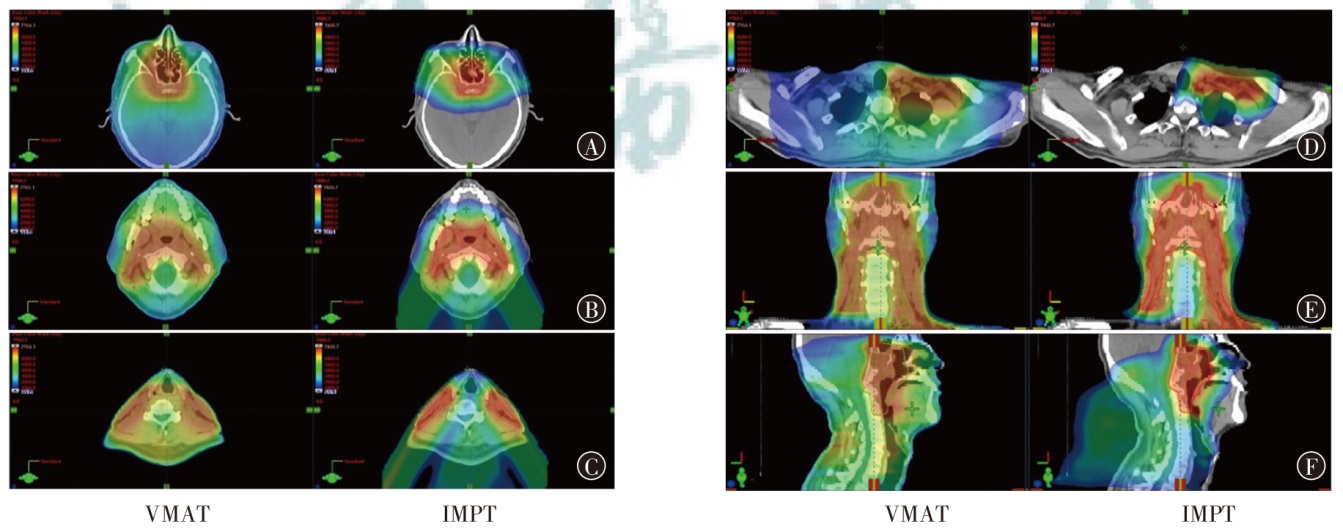

目的探索质子调强放疗(IMPT)和光子容积弧形调强放疗(VMAT)应用于典型头颈部恶性肿瘤的剂量学特点。方法以2023年12月至2024年12月山东省肿瘤防治研究院(山东省肿瘤医院)收治的鼻咽癌、腮腺癌和喉癌患者各1例为研究对象,分别根据靶区和危及器官限值的临床处方要求制定IMPT和VMAT计划。评估3例患者两种计划的靶区适形指数(CI)、均匀性指数(HI)和梯度指数(GI),并评估危及器官的剂量学指标。结果鼻咽癌、腮腺癌和喉癌患者IMPT计划的CI分别为0.70、0.72和0.67,HI分别为0.11、0.08和0.08,GI分别为3.08、2.49和3.75;VMAT计划的CI分别为0.77、0.82和0.91,HI分别为0.12、0.10和0.04,GI分别为3.67、2.63和3.45。IMPT计划的CI略低于VMAT计划,IMPT计划的HI与VMAT计划相当,鼻咽癌和腮腺癌患者IMPT计划的GI低于VMAT计划,喉癌患者IMPT计划的GI高于VMAT计划,且均在临床接受范围。IMPT计划在鼻咽癌、腮腺癌和喉癌治疗中表现出显著的剂量优势:对于鼻咽癌患者,IMPT计划的左、右晶体Dmax比VMAT分别降低了54.1%和50.4%,口腔和喉头的Dmean分别降低了40.5%和49.6%。对于腮腺癌患者,IMPT的脑干和脊髓Dmax比VMAT分别降低了66.2%和40.5%。对于喉癌患者,IMPT的脊髓Dmax比VMAT降低了77.0%,而甲状软骨Dmean比VMAT增加了8.0%。对于患者体内的额外剂量,以患者体内10%、30%和50%的处方剂量区域所占的绝对体积为例,鼻咽癌患者IMPT比VMAT计划分别降低了29.7%、29.6%和34.9%,腮腺癌患者IMPT比VMAT计划分别降低了61.0%、39.7%和17.4%,喉癌患者IMPT比VMAT计划分别降低了63.9%、31.7%和4.1%。结论相比VMAT计划,IMPT计划可有效降低头颈部肿瘤靶区附近大部分危及器官的受照射剂量,但对于紧邻靶区的串型器官,其剂量可能更高,需要引起关注。

ObjectiveTo investigate the dosimetric characteristics of intensity modulated proton therapy (IMPT) and photon volumetric modulated arc therapy (VMAT) in typical head and neck malignant tumors.MethodsThree types of typical head and neck tumors (nasopharyngeal carcinoma, parotid gland carcinoma, laryngeal carcinoma) treated at Shandong Cancer Hospital and Institute from December 2023 to December 2024 were taken as research subjects. IMPT and VMAT radiotherapy plans were created according to clinical prescription requirements of target and organs at risk limits respectively. The conformity index (CI), homogeneity index (HI) and gradient index (GI) for target coverage of two radiotherapy plans were evaluated for 3 patients, as well as the dosimetric indicators of organs at risk.ResultsThe CI of IMPT for nasopharyngeal carcinoma, parotid gland carcinoma and laryngeal carcinoma were 0.70, 0.72 and 0.67, respectively. The HI were 0.11, 0.08 and 0.08, respectively. The GI were 3.08, 2.49 and 3.75, respectively. The CI of VMAT plans were 0.77, 0.82 and 0.91, respectively. The HI were 0.12, 0.10 and 0.04, respectively. The GI were 3.67, 2.63 and 3.45, respectively. The results showed that CI of IMPT plan was slightly lower than that of VMAT plan, and HI of IMPT plan was comparable to that of VMAT plan, the GI of the IMPT plan for patients with nasopharyngeal carcinoma and parotid gland carcinoma was lower than that of the VMAT plan, and the GI of the IMPT plan for patient with laryngeal carcinoma was higher than that of the VMAT plan, and all were within the clinically acceptable range. The IMPT plan has demonstrated significant dose advantages in the treatment of nasopharyngeal carcinoma, parotid gland carcinoma and laryngeal carcinoma. For patient with nasopharyngeal carcinoma, the IMPT plan reduced the Dmaxof the left and right crystals by 54.1% and 50.4%, respectively, compared to VMAT plan, and reduced the Dmeanof the oral and laryngeal tissues by 40.5% and 49.6%, respectively. For patient with parotid gland carcinoma, IMPT plan reduced the Dmaxof the brainstem and spinal cord by 66.2% and 40.5%, respectively, compared to VMAT plan. For patient with laryngeal carcinoma, IMPT reduced spinal cord Dmaxby 77.0%, while thyroid cartilage Dmeanincreased by 8.0% compared to VMAT plan. For the additional dose in the patients' body, taking the absolute volumes occupied by the prescribed dose areas of 10%, 30%, and 50% in the patients' body as examples, IMPT plan of nasopharyngeal carcinoma patient decreased by 29.7%, 29.6%, and 34.9% compared to VMAT plan, respectively. IMPT plan of parotid gland carcinoma patient decreased by 61.0%, 39.7%, and 17.4% compared to VMAT plan, respectively. IMPT plan of laryngeal carcinoma patient decreased by 63.9%, 31.7%, and 4.1% compared to VMAT plan, respectively.ConclusionsCompared with VMAT plan, IMPT plan can effectively reduce the irradiation dose of most organs at risk near the target of head and neck tumors, but the dose of string organs close to the target area may be higher, which needs attention.